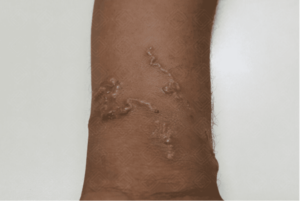

Paciente masculino, jovem, apresenta lesões cutâneas serpiginosas, eritematosas, elevadas e intensamente pruriginosas em extremidade, com progressão diária do trajeto, após contato com solo arenoso contaminado.

Imagem 1: Lesões serpiginosas, eritematosas, elevadas e intensamente pruriginosas, que progridem devido à migração das larvas.

A larva migrans cutânea é uma ectoparasitose decorrente da penetração acidental de larvas de ancilostomídeos na epiderme humana. A migração intraepidérmica do parasita induz resposta inflamatória local, caracterizada por prurido intenso, edema e infiltrado eosinofílico, formando trajetos lineares ou serpiginosos, geralmente autolimitados.